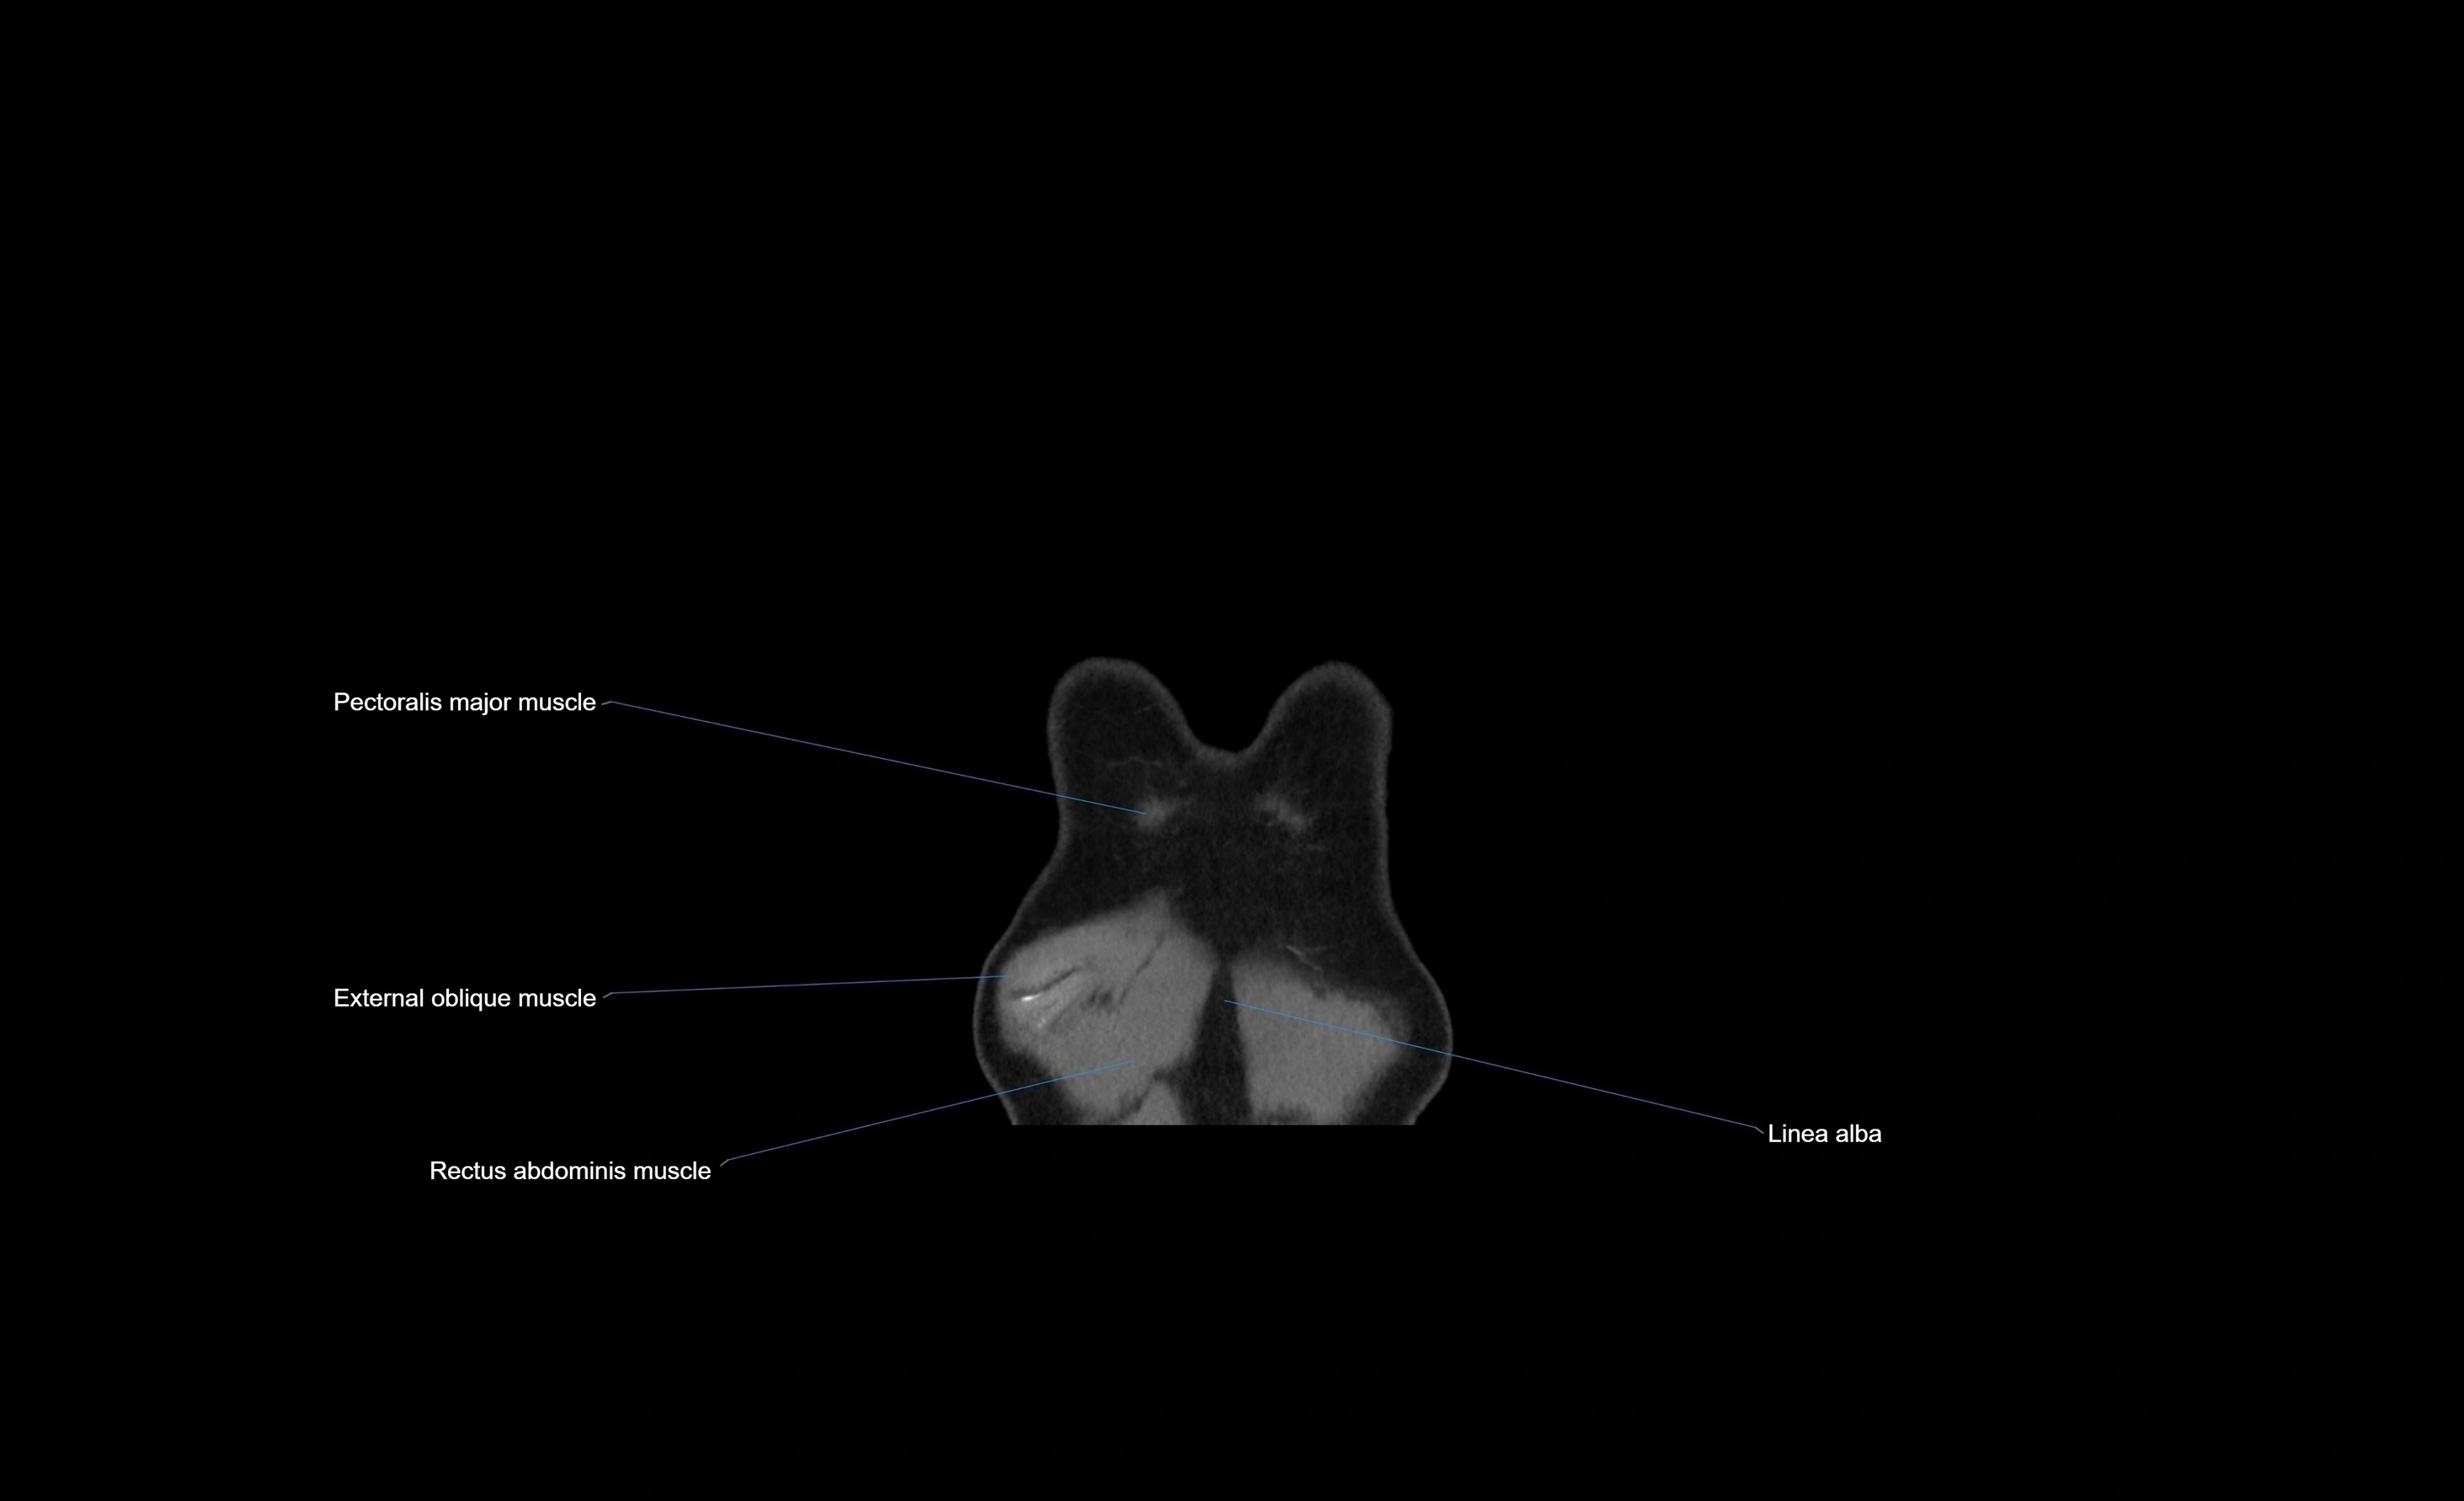

CT images